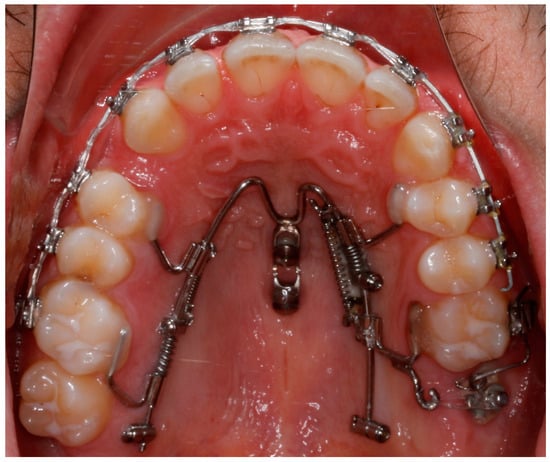

2.1. The Appliance

2.3. Case Description